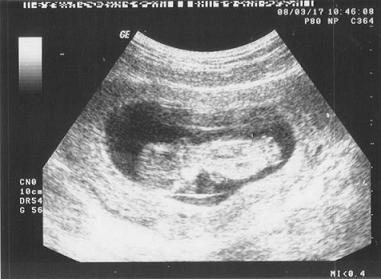

Gratula az uh-okhoz!!! Úgy irigykedem! Persze veletek örültök, de majdmegesz a fene, hogy mikor lesz már ápr. 8.! REmélem, így hogy dolgozom gyorsabban repülnek majd a napok.!